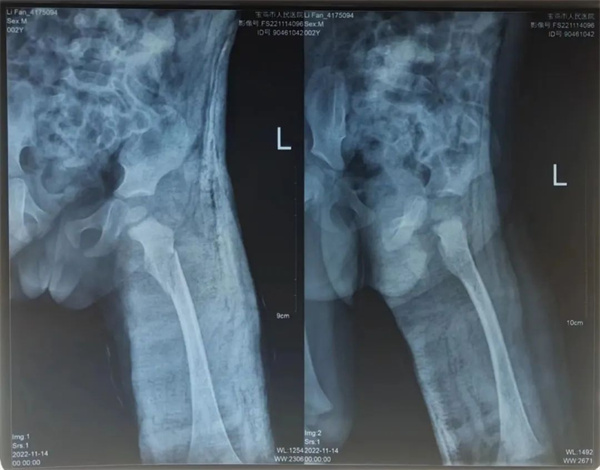

术后恢复一周

术后恢复两周

术后康复治疗期间,科室医护紧密关注患儿情况,从护理、搬动、大小便等方面全方位照顾,防止骨折移位。因为患儿年幼,护士长王艳和主管护士雷晓玲时常来观察、安抚。雷晓玲观察到患儿每次看到透视机器就会紧张、害怕,便为带来了自家孩子的玩具和零食来缓解患儿检查治疗过程中的恐惧心理。在科室医护的悉心治疗照料下,经过三周动态X线复查,患儿骨折端愈合良好,已经长出了骨痂,这就意味着孩子的骨头已经开始愈合了,家人也不用担心骨折处发生移位了。看着孩子一天天多起来的笑容,家属慢慢舒展开的眉头,这大概是科室医护历经三周的辛苦耕耘后最好的收获。